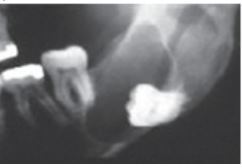

What is Stafne Bone defect?

* A radiolucency in posterior mandible below IAC

* Due to lingual concavity

* May appear as cyst but is not a pathology